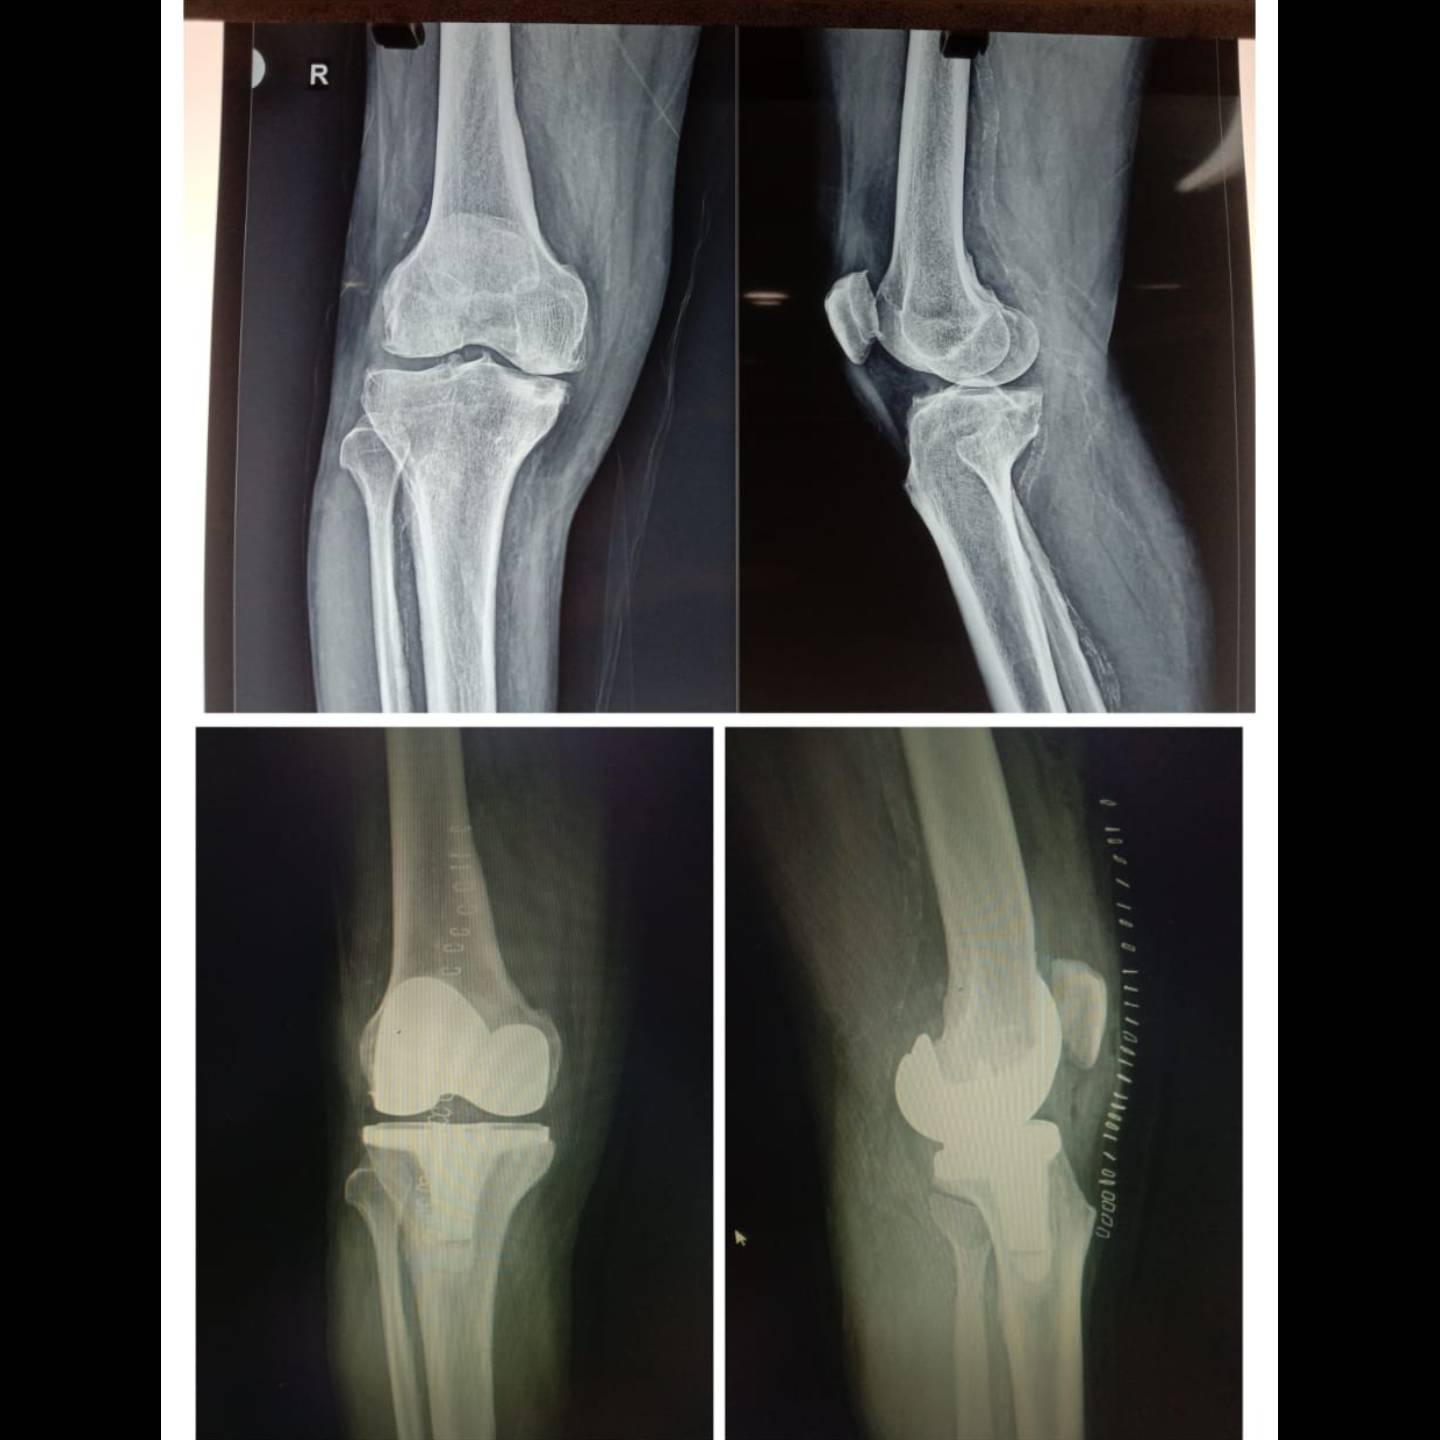

66 y gentleman with severely painful arthritic knee...total knee replacement.

Young female ...with knock knees..before and after complete correction of her deformity.